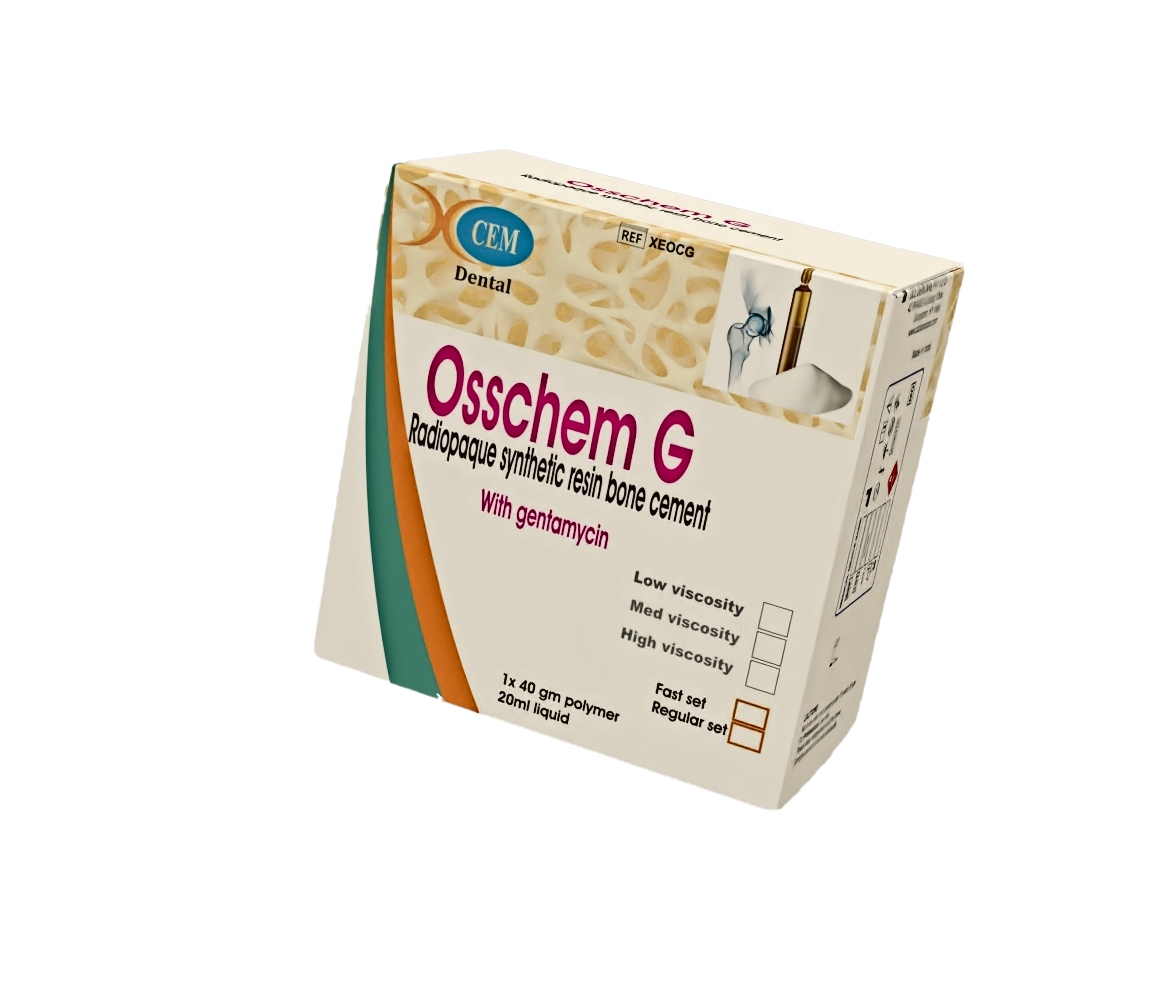

orthopaedic resin bone cement with Gentamycin

DCL oscem Bone Cement

Bone cement is used for fixation of orthopaedic prosthesis to bone..

It is PMMA (polymethylmethacrylate) cement